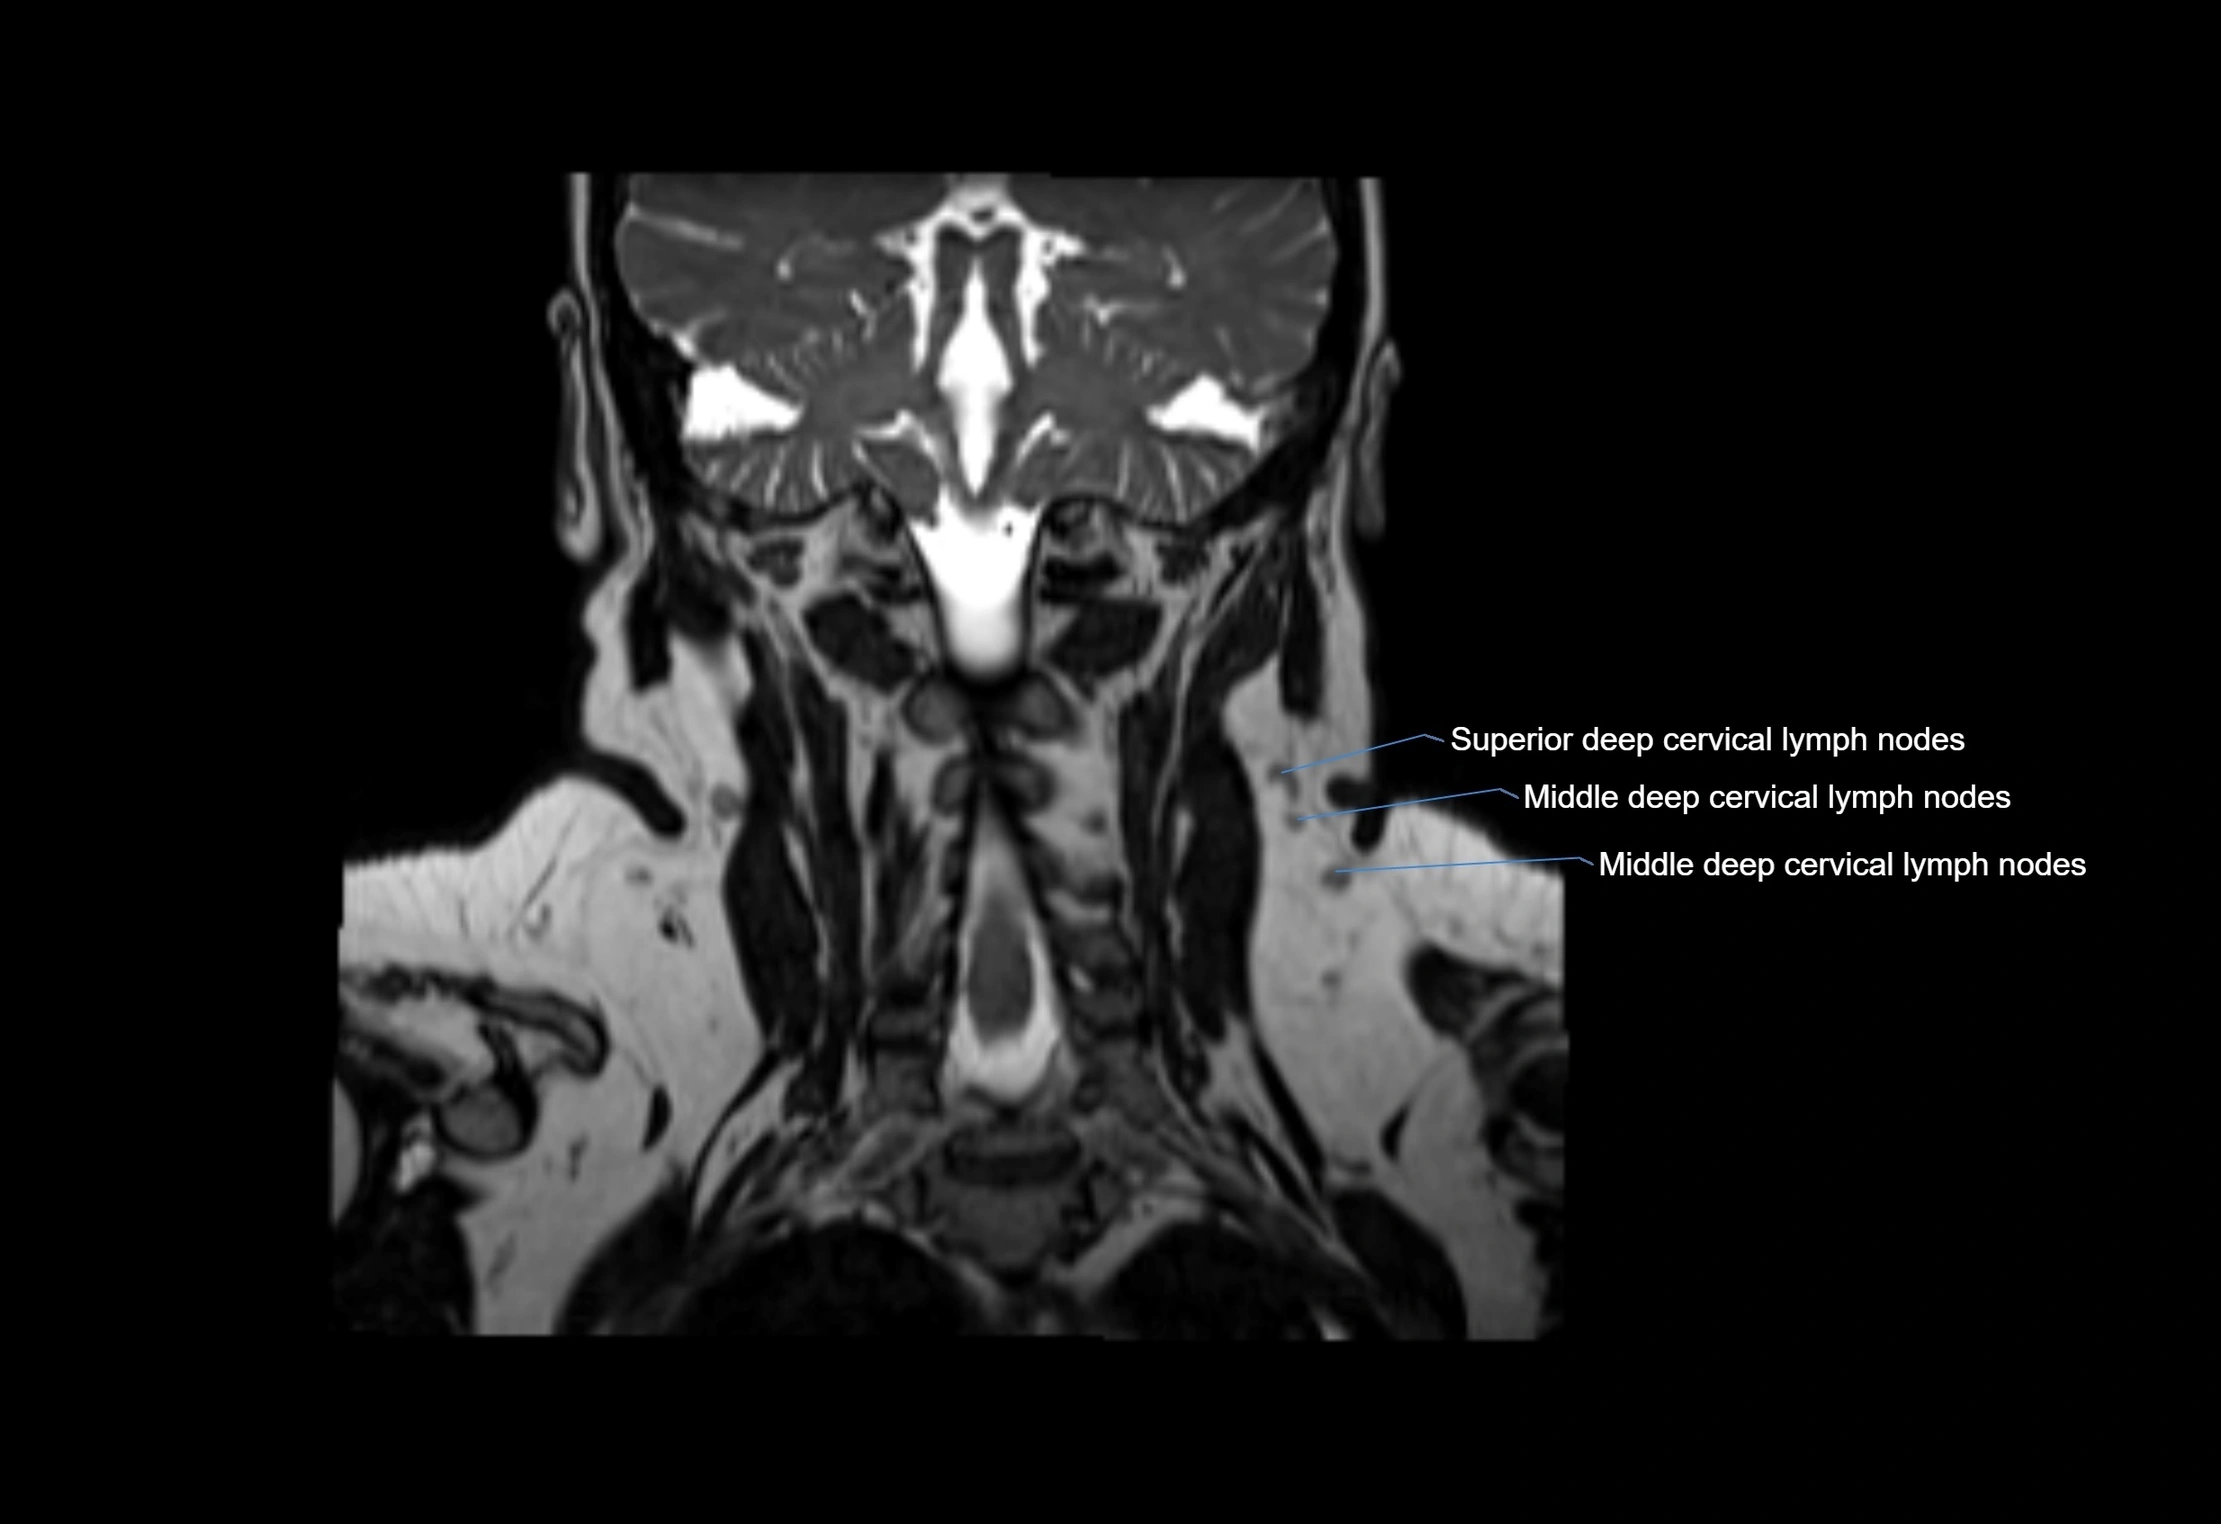

Accessory lymph nodes are small, secondary lymph nodes located along the main facial and cervical lymphatic chains, often adjacent to primary lymph nodes, such as preauricular, submandibular, or occipital nodes. They are typically less than 5 mm in diameter, embedded within subcutaneous fat or connective tissue, and may be variable in number and location. These nodes provide additional filtration and immune surveillance for lymph collected from the face, scalp, and neck regions. Accessory lymph nodes are usually non-palpable in healthy individuals but may enlarge in response to infection, inflammation, or metastasis, making them clinically significant.

• Found along primary lymph node chains, including preauricular, submandibular, parotid, and occipital regions

• Embedded in subcutaneous fat or superficial fascia, often lateral or posterior to primary nodes